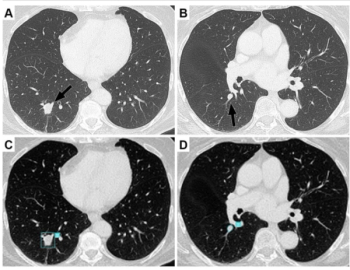

A machine-learning-based model demonstrated an 87 percent area under the curve and a 90 percent specificity rate for predicting interstitial lung abnormality on CT scans, according to new research.